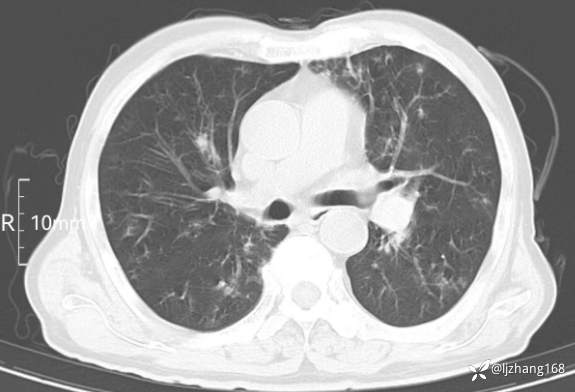

老年男患,咳嗽,气短,双肺多发间质性病变,何种感染?(有结果)

辅助检查:胸部CT:双肺肺气肿,间质性病变,血气分析:PH 7.413, PCO2 29.2mmHg, PO2,81.8mmHg,乳酸 3.3mmol/1,剩余碱-4.0mmol/1,HC03 18.8mmol/1。全血超敏C反应蛋白:超敏C反应蛋白 135.60 mg/L、 白细胞 14x19^9/L,中性粒细胞11.6x10^9/L。